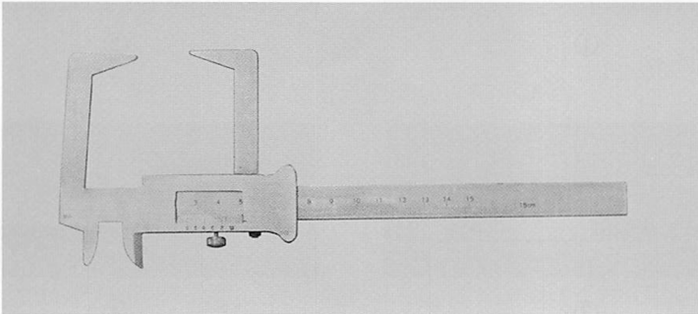

全部床義歯の製作時に用いる器具の写真を別に示す。 この器具を用いるのはどれか。1つ選べ。

a.概形印象採得

b.筋圧形成

c.下顎安静位の測定

d.水平的顎間関係の記録

解答を見る

c